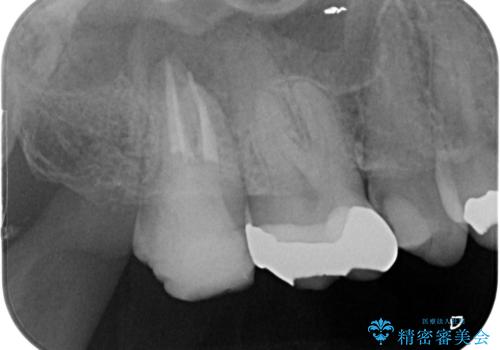

レントゲンと,CT撮影を行なったところ右上小臼歯が虫歯、右上第二大臼歯には根の先に大きな病気がありました。

手前の歯はセラミック治療を行い、奥の歯は精密根管治療を行いゴールドクラウンで治療を行いました。

根管治療はラバーダム防湿を行い、無菌的な状態で治療を行っています。

CTでは経過良好で経過観察を行なっていきます。